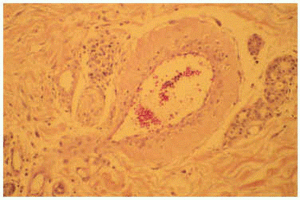

Un cultivo del exudado de una úlcera aisló Staphylococcus aureus, aunque el tratamiento antibiótico no modificó la evolución del cuadro. El estudio histopatológico de una lesión ulcerosa de reciente aparición, localizada en brazo, mostró una alteración en cuña con una úlcera superficial acompañada de un denso infiltrado inflamatorio difuso en el área superficial constituido por linfocitos, histiocitos y neutrófilos. En el vértice de la cuña, situado en la unión dermohipodérmica, se apreciaba una arteriola que contenía un trombo de fibrina que ocluía por completo la luz (fig. 2). A ese nivel se observaban escasas células inflamatorias sin relación con el vaso. Alrededor de la úlcera, se observaban diversas alteraciones en los vasos sanguíneos. Algunos vasos de la dermis mostraban una luz dilatada con una pared engrosada que contenía un material hialino (fig. 3), mientras que otros presentaban una luz estrecha con una pared rodeada de fibrina, muchos de ellos con trombos intraluminales.

Fig. 2.--Caso 1. Arteriola localizada en el unión dermoepidérmica, en el ápex de la úlcera. En este punto se observa escaso infiltrado inflamatorio que no estaba en relación con el vaso; sin embargo, se aprecia un trombo de fibrina en su luz.